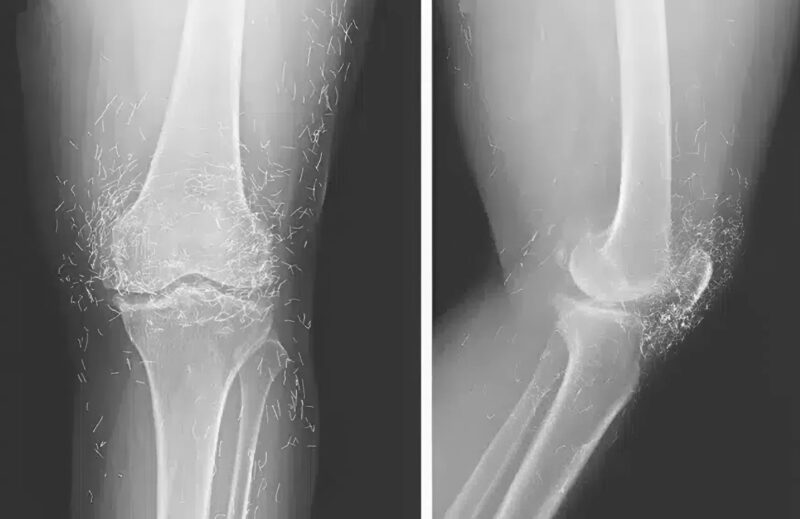

When the images arrived, everything changed. The nurse who brought them in froze by the door. “Doctor… you need to see this.” I took the envelope, pulled out the film, and held it against the light. For a second, I couldn’t comprehend what I was looking at. Her knee joint shimmered with dozens of tiny, metallic streaks — arranged in perfect symmetry.

At first, I thought it was an error — maybe a reflection, a machine glitch. We repeated the scan. The same strange pattern appeared again. I adjusted the magnification, leaned closer to the screen… and then felt a chill run down my spine. Those streaks weren’t reflections. They were real. They were inside her. 😱

When she finally came to us, the inflammation was advanced. The X-rays showed what her faith had hidden: over thirty golden needles embedded in soft tissue, surrounded by infection and scar. The body had fought them all these years — forming capsules of fibrous tissue around each invader, as if building tiny prisons inside her flesh. But some capsules had ruptured, releasing toxins.

We scheduled emergency surgery. Under anesthesia, I studied her knee one last time on the monitor. The needles sparkled like constellations — Orion, Cassiopeia, stars trapped beneath her skin. 🌌 The image was hauntingly beautiful and unbearably tragic.